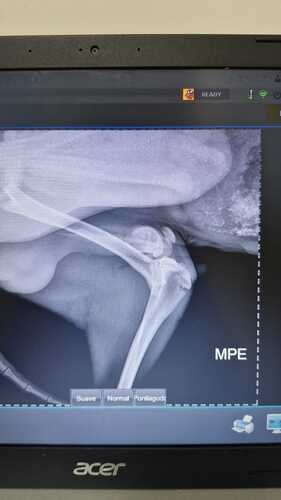

Nós, Rafael e Isabela, não pensamos duas vezes e o levamos imediatamente ao veterinário Dra.Vet. O diagnóstico foi devastador: Pingo quebrou as duas patinhas traseiras e precisa de uma cirurgia urgente para voltar a andar. A boa notícia? Ele tem grandes chances de recuperação, pois, apesar do acidente, nenhum órgão interno foi afetado!